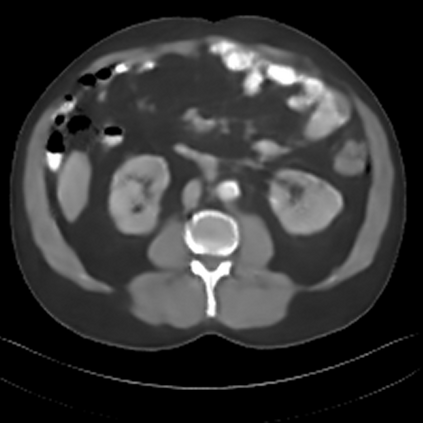

Sparse-view computed tomography (CT) -- using a small number of projections for tomographic reconstruction -- enables much lower radiation dose to patients and accelerated data acquisition. The reconstructed images, however, suffer from strong artifacts, greatly limiting their diagnostic value. Current trends for sparse-view CT turn to the raw data for better information recovery. The resultant dual-domain methods, nonetheless, suffer from secondary artifacts, especially in ultra-sparse view scenarios, and their generalization to other scanners/protocols is greatly limited. A crucial question arises: have the image post-processing methods reached the limit? Our answer is not yet. In this paper, we stick to image post-processing methods due to great flexibility and propose global representation (GloRe) distillation framework for sparse-view CT, termed GloReDi. First, we propose to learn GloRe with Fourier convolution, so each element in GloRe has an image-wide receptive field. Second, unlike methods that only use the full-view images for supervision, we propose to distill GloRe from intermediate-view reconstructed images that are readily available but not explored in previous literature. The success of GloRe distillation is attributed to two key components: representation directional distillation to align the GloRe directions, and band-pass-specific contrastive distillation to gain clinically important details. Extensive experiments demonstrate the superiority of the proposed GloReDi over the state-of-the-art methods, including dual-domain ones. The source code is available at https://github.com/longzilicart/GloReDi.